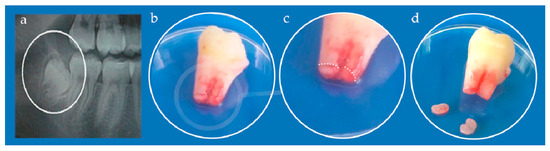

The study was approved by the Ethical Committee of the School of Dental Medicine, University of Belgrade (No 36/19). Immature, impacted third lower molar was extracted from a teenage patient at the Clinic for Oral Surgery (Figure 3), School of Dental Medicine, University of Belgrade, after signing the informed consents by patient’s parents. Stem cells from apical papilla were isolated as previously described [34]. Briefly, extracted tooth was rinsed with Dulbecco’s Phosphate-Buffered Saline (DPBS, Thermo Fisher Scientific, Waltham, MA, USA), and apical papilla was separated from the root apex and transferred into T-25 flasks after mincing. The tissues were grown in cell complete medium (DMEM supplemented with 10% fetal bovine serum and 1% antibiotic-antimycotic solution). Cells were cultured under standard conditions (37 °C, 95% air–5% CO2 atmosphere, 95% humidity) and growth medium was changed every third day. All following experiments were carried out with the cells from the fourth and fifth passage.

Figure 3. (a) Orthopantomogram of right mandibular impacted third molar (encircled); (b) Extracted tooth; (c) Detail from (b) white dotted line depicts border between apical papilla (lower parts) and tooth root (upper part); (d) Kidney-shaped apical papilla tissues separated from the tooth.